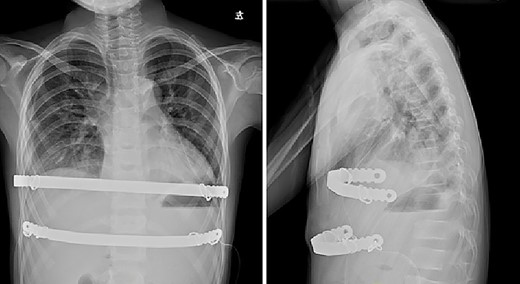

The patient was a 7-year-old boy. Two years ago, he underwent surgical treatment for pectus excavatum in a local hospital. At that time, Wang procedure was used and a steel bar was implanted. After the operation, the steel bar was displaced and the depression recurred (Figs 1 and 2), so the steel bar had to be taken out 1 year after the operation. After removal, his anterior chest wall still had obvious depression, and there was a tendency to aggravate. In order to completely correct the deformity, the patient was recently admitted to our hospital for surgery. Preoperative physical examination showed that the anterior chest wall was asymmetrically depressed, and the deepest depression was located in the right chest wall (Fig. 3). There was a scar in the middle of the anterior chest wall (Fig. 3). Preoperative imaging examination showed that the anterior chest wall was depressed, the heart was obviously compressed and moved to the left (Fig. 4). The operation was performed under general anesthesia. Supine position was adopted, with abduction of both upper limbs. Two incisions were made on both lateral chest wall respectively, which were located at the deepest plane of the depression. The muscles were dissected to expose the ribs in the incision. The depression was eliminated by Wung procedure, which was performed as follows [2]: A tunnel at the deepest plane of the depression was made. A special guider was inserted directly through the gap between the sternum and the heart, and then a steel bar introducing tube was connected with the guider. After the introducing tube was pulled into the body by the guider, a special steel bar was pulled by the introducing tube to the bottom of the depression. After the steel bar was rotated, the depression was supported, but the left chest wall began to be protrusive. In order to make the anterior chest wall more beautiful, Wenlin procedure was performed next [3, 4]. An incision at the median scar was made, and a tunnel was built from the median incision to the incision on both sides, which was located between the bone structures and the chest wall muscles. The second steel bar was inserted into the tunnel. After the protrusive part of the anterior chest wall was pressed with the middle part of the steel bar, both sides of the bar was fixed to the ribs on the lateral chest wall. Drainage tubes were placed in the thoracic cavity on both sides, the incision was closed, and the operation was completed (Fig. 5). No complications occurred during the operation. The total operation time was 50 min and the intraoperative bleeding volume was 5 ml. Postoperative X-ray examination showed that the positions of the steel bars were satisfactory and the shape of the chest wall was basically normal (Fig. 6). The patient was discharged 5 days after operation. Follow up for 1 month showed no change in thoracic shape and no discomfort.